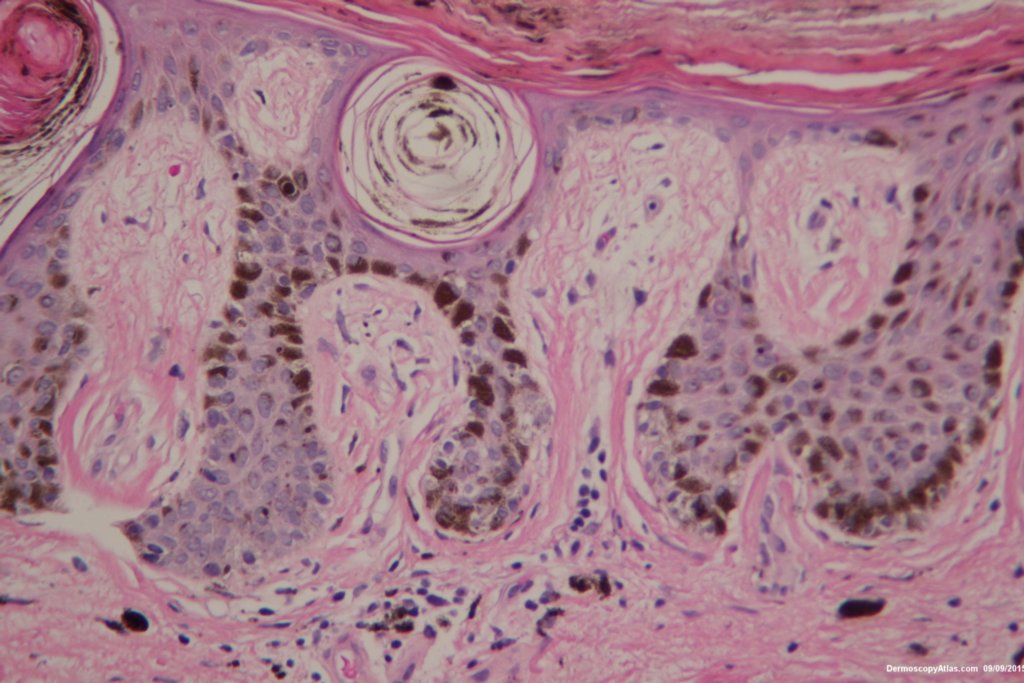

Diagnosis: Nevus junctional dysplastic lentiginous

Patient aged 92 noted to have this new lesion on the lower back. Note the extruded melanin on the stratum corneum and the lentiginous spread of melanocytes at the dermo epidermal junction. The dermatoscopy is symmetrical with multiple central clods presumably from the pigment in the stratum corneum. Tape stripping would have helped here.

Reported as a benign dysplastic junctional nevus. Special stains failed to show any upward spread of the melanocytes.